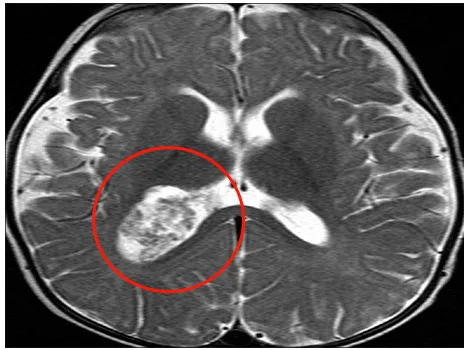

INC鲁特卡教授也曾为一名脉络丛乳头状瘤患儿进行手术——磁共振成像(MRI)显示,奥利佛右侧脑室后角有一个大肿块,考虑脉络丛乳头状瘤病变,并有蒂连接,伴有中度脑积水。

鲁特卡教授通过右顶骨开颅手术和侧脑室切开后中央回后方的皮质切口。暴露血管高度丰富的肿瘤,逐块切除肿瘤。

经过鲁特卡教授的手术治疗,奥利佛康复得十分顺利。两周后,奥利佛的所有体征和症状术后均已缓解。CT扫描结果显示,脑积水减少,脉络丛正常。他平安出院,术后也无需任何辅助治疗。